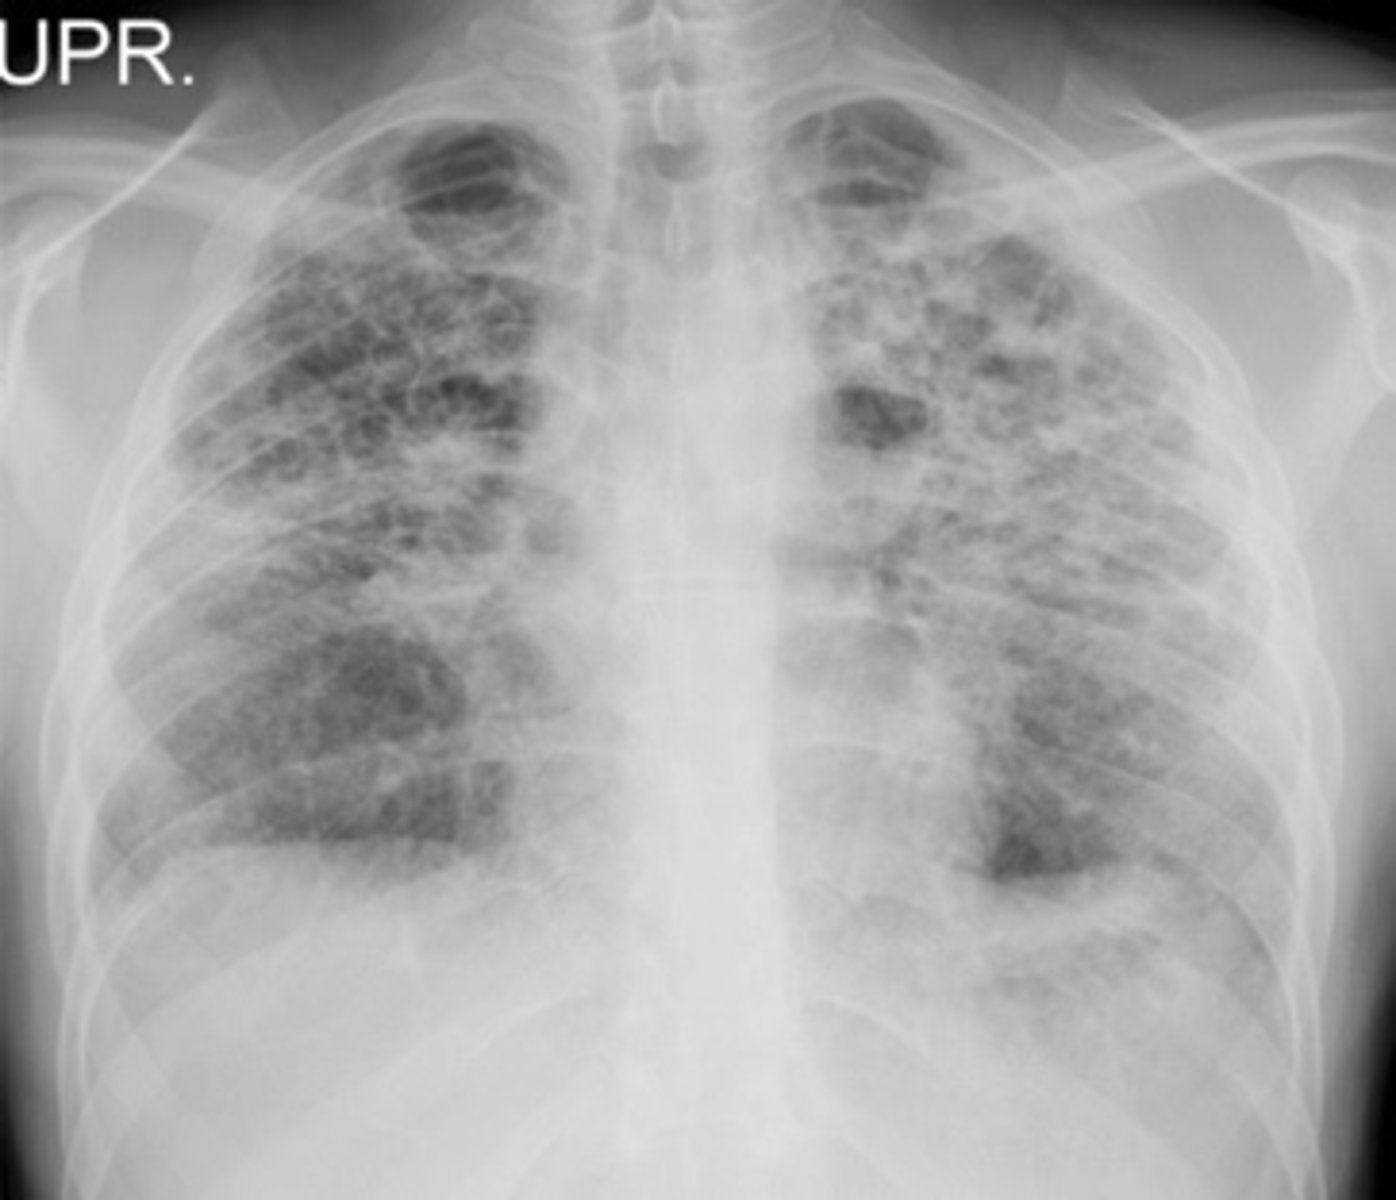

Bilateral interstitial infiltrates